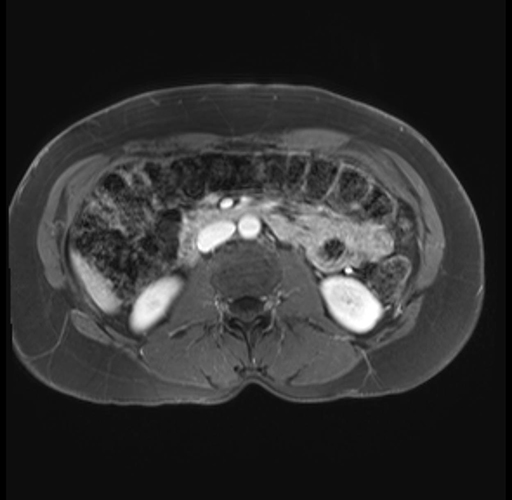

Imaging Analysis

Look through the patient's CT scan to identify any areas of concern for the necessary procedure.

Based on your CT findings, which issue(s) are present and would give reason for "planned slowing down moment(s)" in this case?